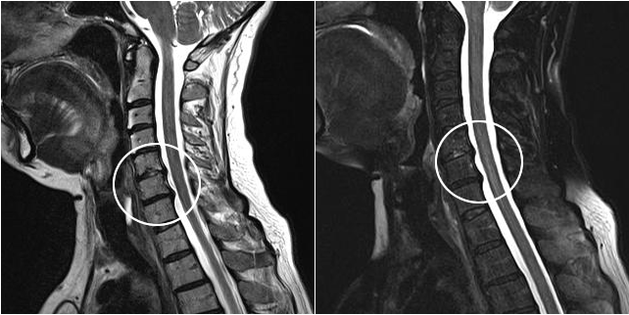

Modern diagnostic methods include MRI and CT, which allow you to more precisely examine the processes of destruction of cartilage and bone tissue.In addition, using this technique it is convenient to diagnose hernias and other soft tissue defects near the source of the disease.